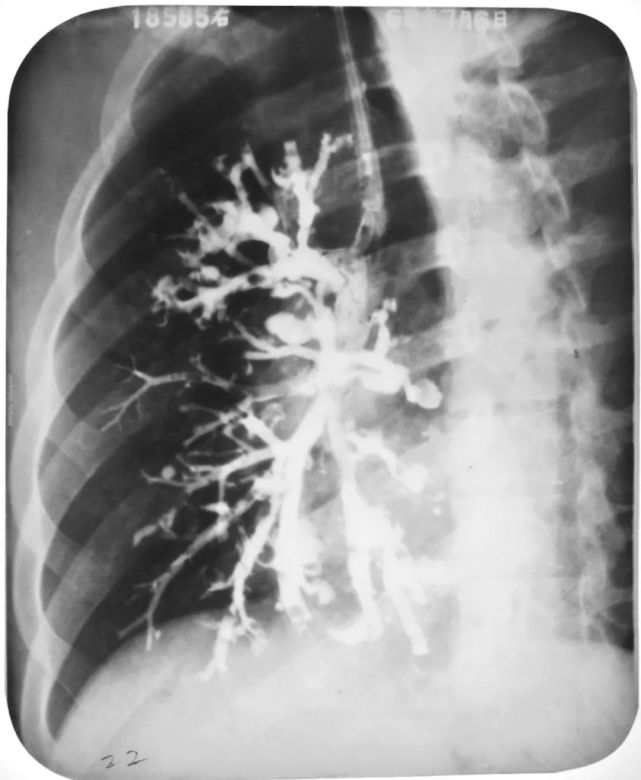

左下叶支气管扩张

图片

左下叶支气管囊状、柱状扩张